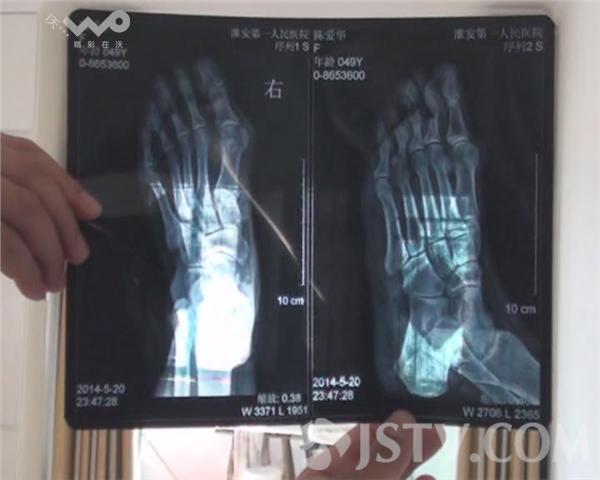

当记者来到陈女士家时,陈女士向记者展示了自己被瓷砖砸伤的右脚,食指和中指骨折,据陈女士介绍,自己用几十万所购买的房子是留给儿子结婚的新房,准备6月份结婚用的,从四月份开始就发现房屋内出现裂缝,昨晚洗澡时就发生了瓷砖脱落伤人。